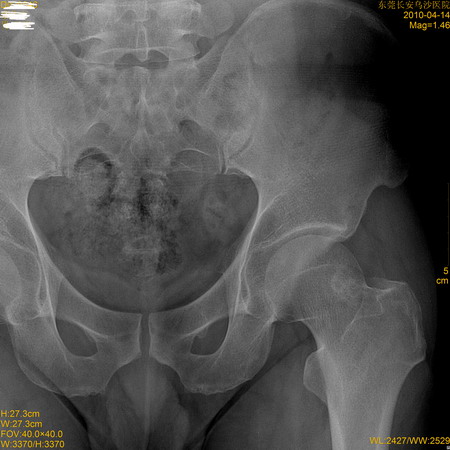

标题: X7186:意外发现

外伤来照片,发现左侧股骨颈小囊状改变

青中年男性,考虑骨纤,建议ct

股骨颈囊疝?

左侧股骨颈骨岛

股骨颈囊疝。不用处理。

股骨颈滑囊疝。一般无临床症状。

此例边界不清,密度较高,年龄不大,临床无症状,不支持滑膜疝囊。

病变位于股骨颈外上象限--股骨颈滑膜疝

左侧股骨颈疝窝。